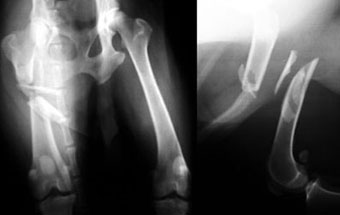

体重4kgの子犬(3か月齢)の大腿骨らせん骨折。

大腿骨中央部分で斜めに折れており、骨折部膝側にはひびが斜めに入っていました。

骨プレートと骨スクリュー6本を使い、コンプレッションプレート法で固定しました。3〜6か月齢の子犬の場合は、3か月程後にプレートを取ります。

写真上段: 手術前

写真下段: 手術後 |